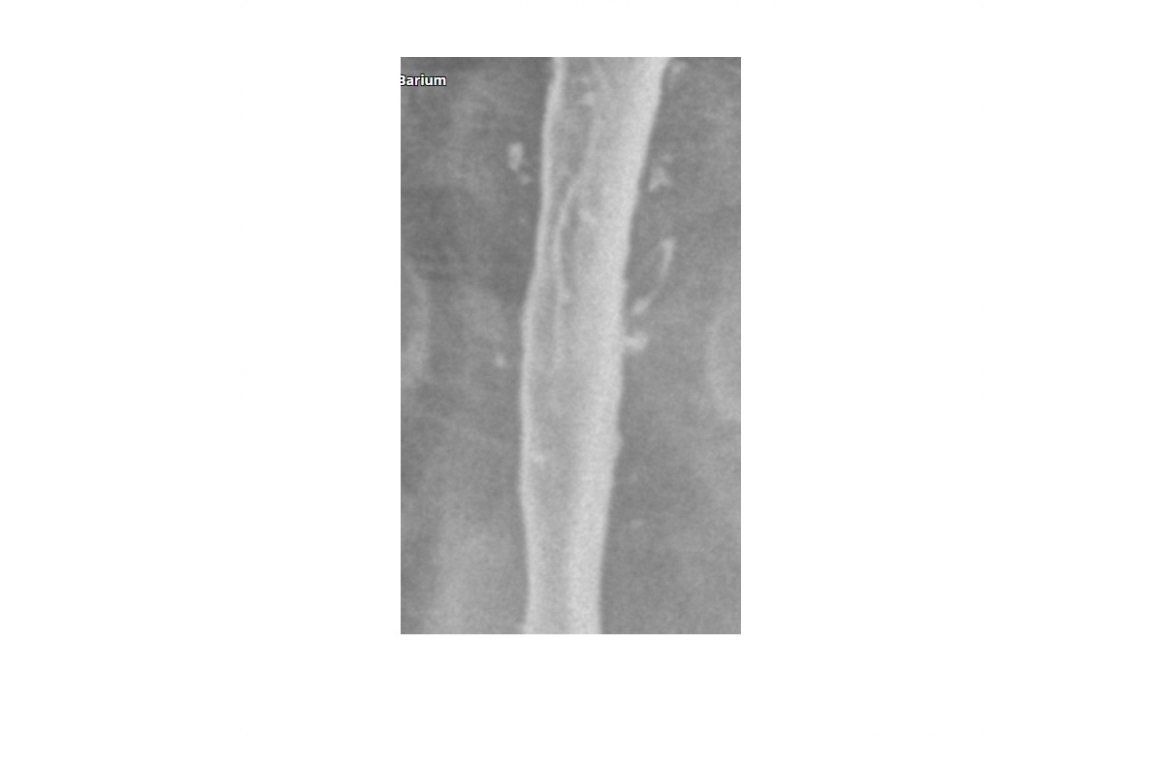

Eosinophilic oesophagitis

Barium - Concentric, ring-like strictures of oesophagus

**Not transient - Permanent **

DDx

feline oesophagus

- folds1-2 mm thick and run horizontally around the entire circumference of the esophageal lumen.

- The findings are transient, seen following reflux and not during swallowing.

- Associated with GORD

- distal two-thirds of the thoracic esophagus